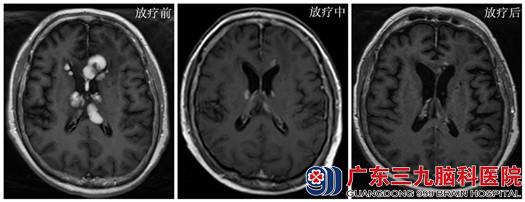

2014年10月1日放疗1.8Gy后神志转清,2014年10月7日放疗10.8Gy后神志清,可自行进食,2014年10月19日放疗 27Gy后神清,查体配合,可扶行,放疗足量后复查肿瘤基本消失,患者可自行行走。